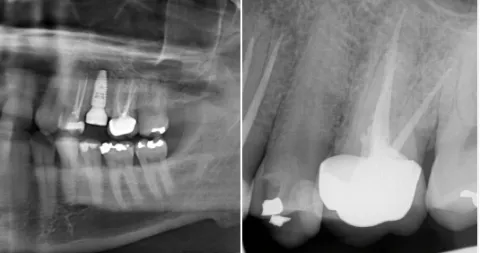

Direktimplantat efter tandutdragning – ett kliniskt exempel på när det lönar sig att vänta Direktimplantat efter tandutdragning är en behandlingsmetod som innebär att ett tandimplantat placeras direkt i alveolen efter att en tand tagits bort. När det används korrekt kan det ge mycket goda resultat med kortare behandlingstid och färre kirurgiska ingrepp. Men som med […]

Direktimplantat efter tandutdragning – Så lyckades vi i ett svårt fall